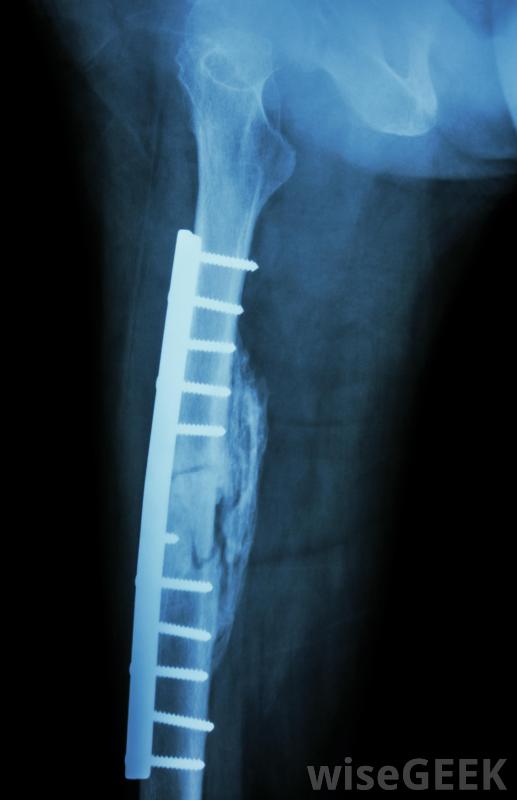

股骨骨折固定手術在大多數情況下被稱為擴髓股骨釘這包括沿著股骨的軸,穿過骨折部位,用X光檢查它的位置。接下來,用一種被稱為鉸刀的切割工具為釘子掏出一條通道。最后,股骨釘插入骨頭并固定到位。

將小塊脂肪送入循環,有時會因血管阻塞和組織損傷而造成致命后果。為此,一些外科醫生傾向于使用未擴髓的股骨釘技術。盡管如此,擴髓股骨釘通常被認為更有優勢,由于未讀法與更多骨愈合延遲和骨無法愈合的病例相關。

股骨釘的替代方法是使用金屬板和骨螺釘